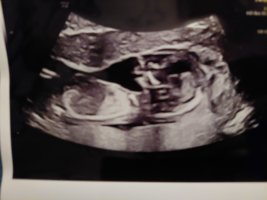

Du er fortsatt 12+1.. Du vet jo fra innsett. Men at fosteret vokser i rykk å napp er ikke uvanlig.. blitt målt lengre alle gangene.Regnet ut i fra IVF egginnsett 12+1, men jordmor mente 12+4 etter å ha målt fosteret da disse bildene ble tatt

Regnet ut i fra IVF egginnsett 12+1, men jordmor mente 12+4 etter å ha målt fosteret da disse bildene ble tatt